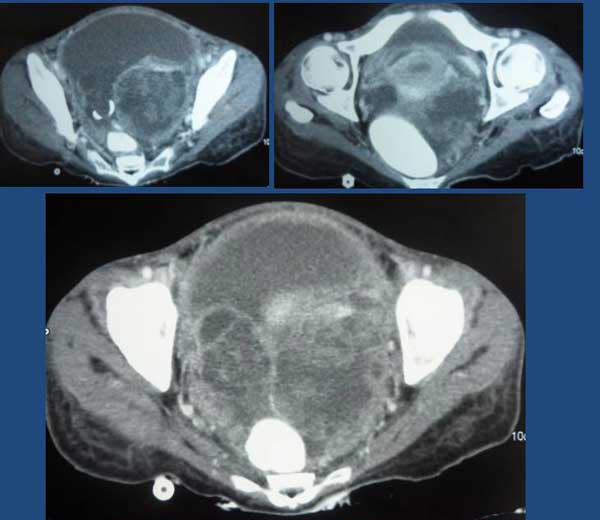

Tag (not real name) was a 59-year-old man from Indonesia. In April 2011, he had coughs with itchy throat. He went to see his doctors and was give medication but these did not help. In August 2011, he came to Penang for further consultation. A CT scan on 22 August 2011 showed an irregular mass (6.6 x 8.0 cm) in the upper left lung extending to the pulmonary hilum with left hilar and mediastinal adenopathy. He also complained of pain in the left pelvis. MRI done on 6 September 2011 showed lesion at the body of C6, body and left pedicle of the L5 vertebra. This was probably metastatic in nature. The doctor said Tag had a Stage 4 cancer.

In the meantime while in the hospital, Tag’s wife came to CA Care and asked for our opinion. The following are the images of his CT and PET scans.

Tag’s wife told me that after a few days on antibiotics infusion, the doctor planned to do a PET scan. I objected to this idea. What is the whole rationale of doing scan over and over again? Know that all these procedures are not good for cancer patients. Do it only if it is absolutely necessary. Just two months ago, you did a CT scan. Now you want to do it again. What do you expect to see and get?

Unfortunately, the next day my wife received a SMS informing us the Tag would want to go ahead and do the PET scan!